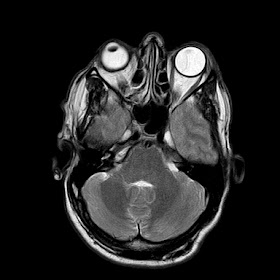

A 35 years old man MRI